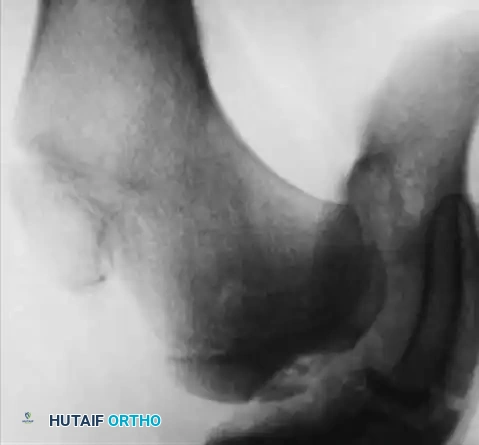

Hemophilic pseudotumors are rare but limb-threatening complications caused by recurrent bleeding into muscles or subperiosteal spaces, leading to pressure necrosis of adjacent bone. In the pediatric hip, recurrent bleeding can compromise the vascular supply to the femoral head, leading to changes indistinguishable from Legg-Calvé-Perthes disease or severe osteochondritis dissecans.

Fig. 29-34: Progression of osteochondritis dissecans of the hip in a hemophilic patient. Note the onset of Perthes-like disease, fragmentation, reossification, and eventual healing over an 8-year period, demonstrating the profound impact of intra-articular pressure and vascular compromise on the developing femoral head.